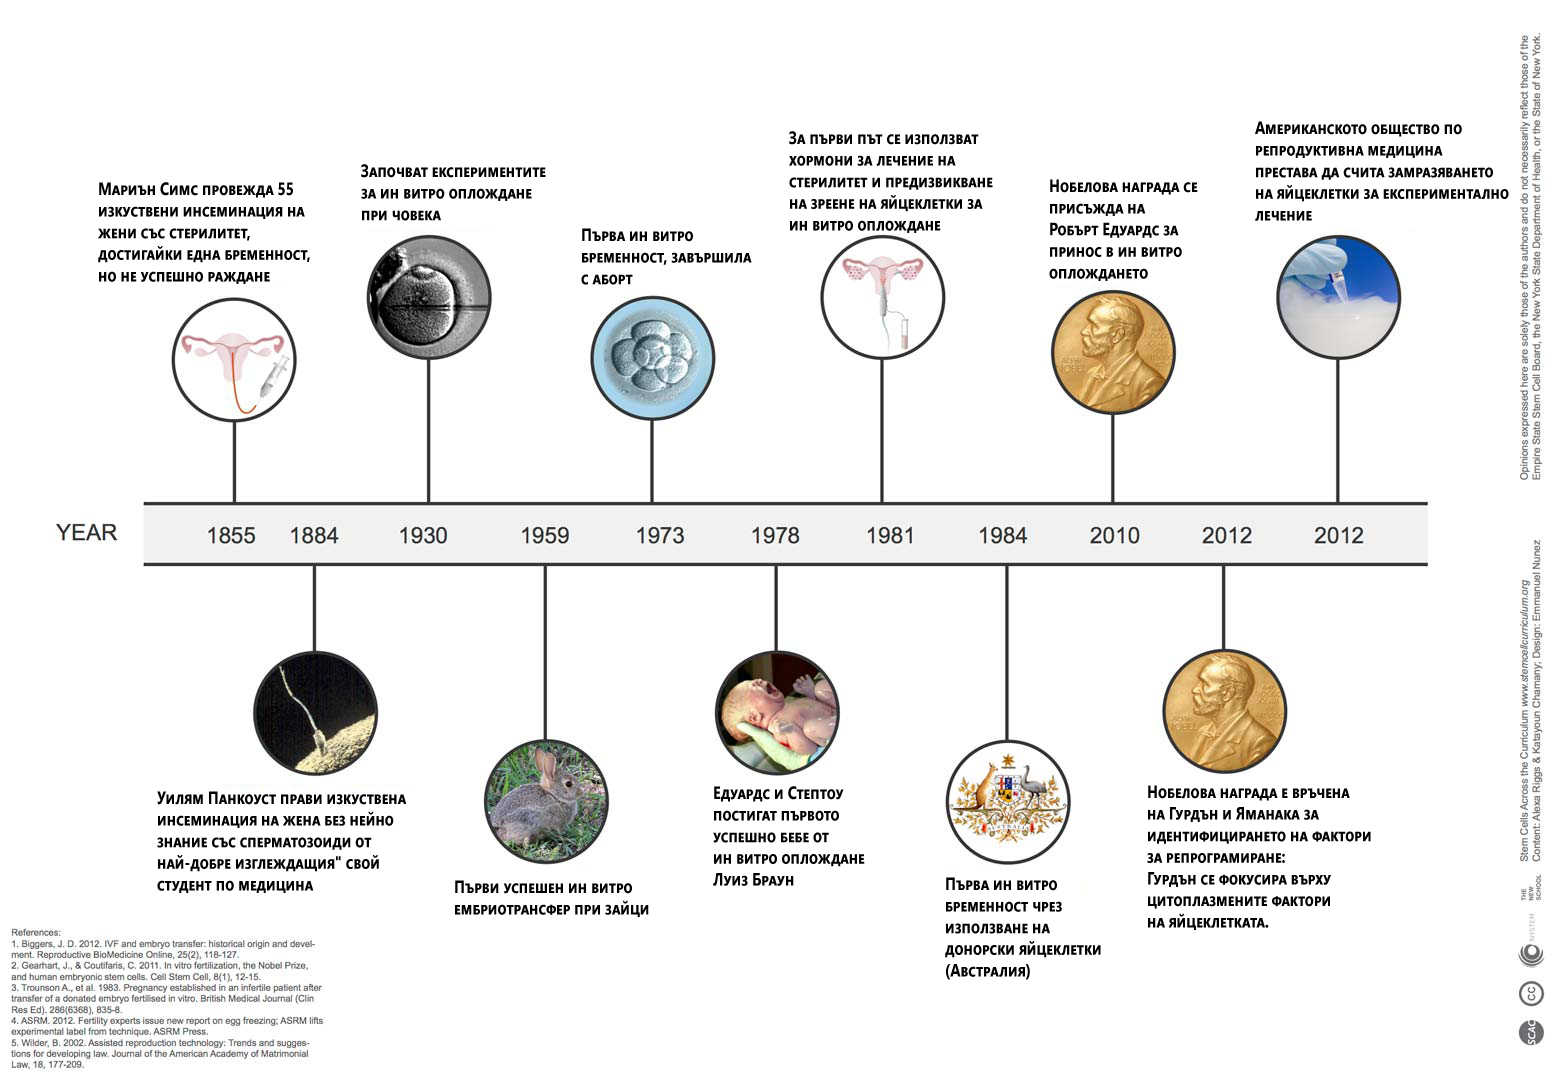

Това лечение позволява на двойки с различни репродуктивни проблеми да заченат, а в днешни дни помага и на еднополови двойки и самотни майки да имат деца. Технологичният напредък в репродуктивната сфера води до раждането на повече от пет милиона бебета според проучване от 2013 година. (Бел. ред. През 2017 вече са 6,5 милиона).

Но през 1978 година, лечението било експериментално. Д-р Макнами, директор на първата в света ин витро клиника “Борн хол” в Кембридж, вярва че Лиуз “е истинско чудо”.

Двамата мъже пионери в областта, гинекологът Партик Стептоу и носителят на нобелова награда физиолог Робърт Едуардс “са направили стотици ембрионални трансфери преди да успеят със зачеването на Луиз”, добавя той. Двамата обединяват усилията си цели 10 години по-рано. Те имат умения, които чудесно се допълват:

Едуардс има успехи в оплождането в лабораторни условия, а Стептоу разработва метод за извличане на яйцеклетки от яйчниците.

“Щом веднъж Стептоу и Едуардс успяват да оплодят яйцеклетка, те много бързо разбират, че трябва да ограничат броя получени ембриони за трансфер, за да намалят вероятността за многоплодна бременност”, обяснява Макнами. “Развитието на крио технологиите през 80те години довело до трансфер само на 1-2 ембриона и замразяването на останалите за бъдеща употреба. По този начин се спестява повторно извличане на яйцеклетки.”

Техниката за директно инжектиране на сперматозоид в яйцеклетката, разработена в края на 80те, е пробив в лечението на мъжкия стерилитет.

Тези, както и други по-малки, подобрения водят до постепенно повишаване на шансовете за зачеване при ин витро цикли. През 80те, когато първата работа на д-р Макнами била да смесва яйцеклетката със спрематозоидите в блюдо на Петри, успеваемостта е едва 10%, сега е около 40%.

Шансовете за зачеване чрез ин витро намаляват с напредването на възрастта, но процесът сега е по-успешен от естествено зачеване в даден цикъл. Но все още няма всеобощо одобрение.